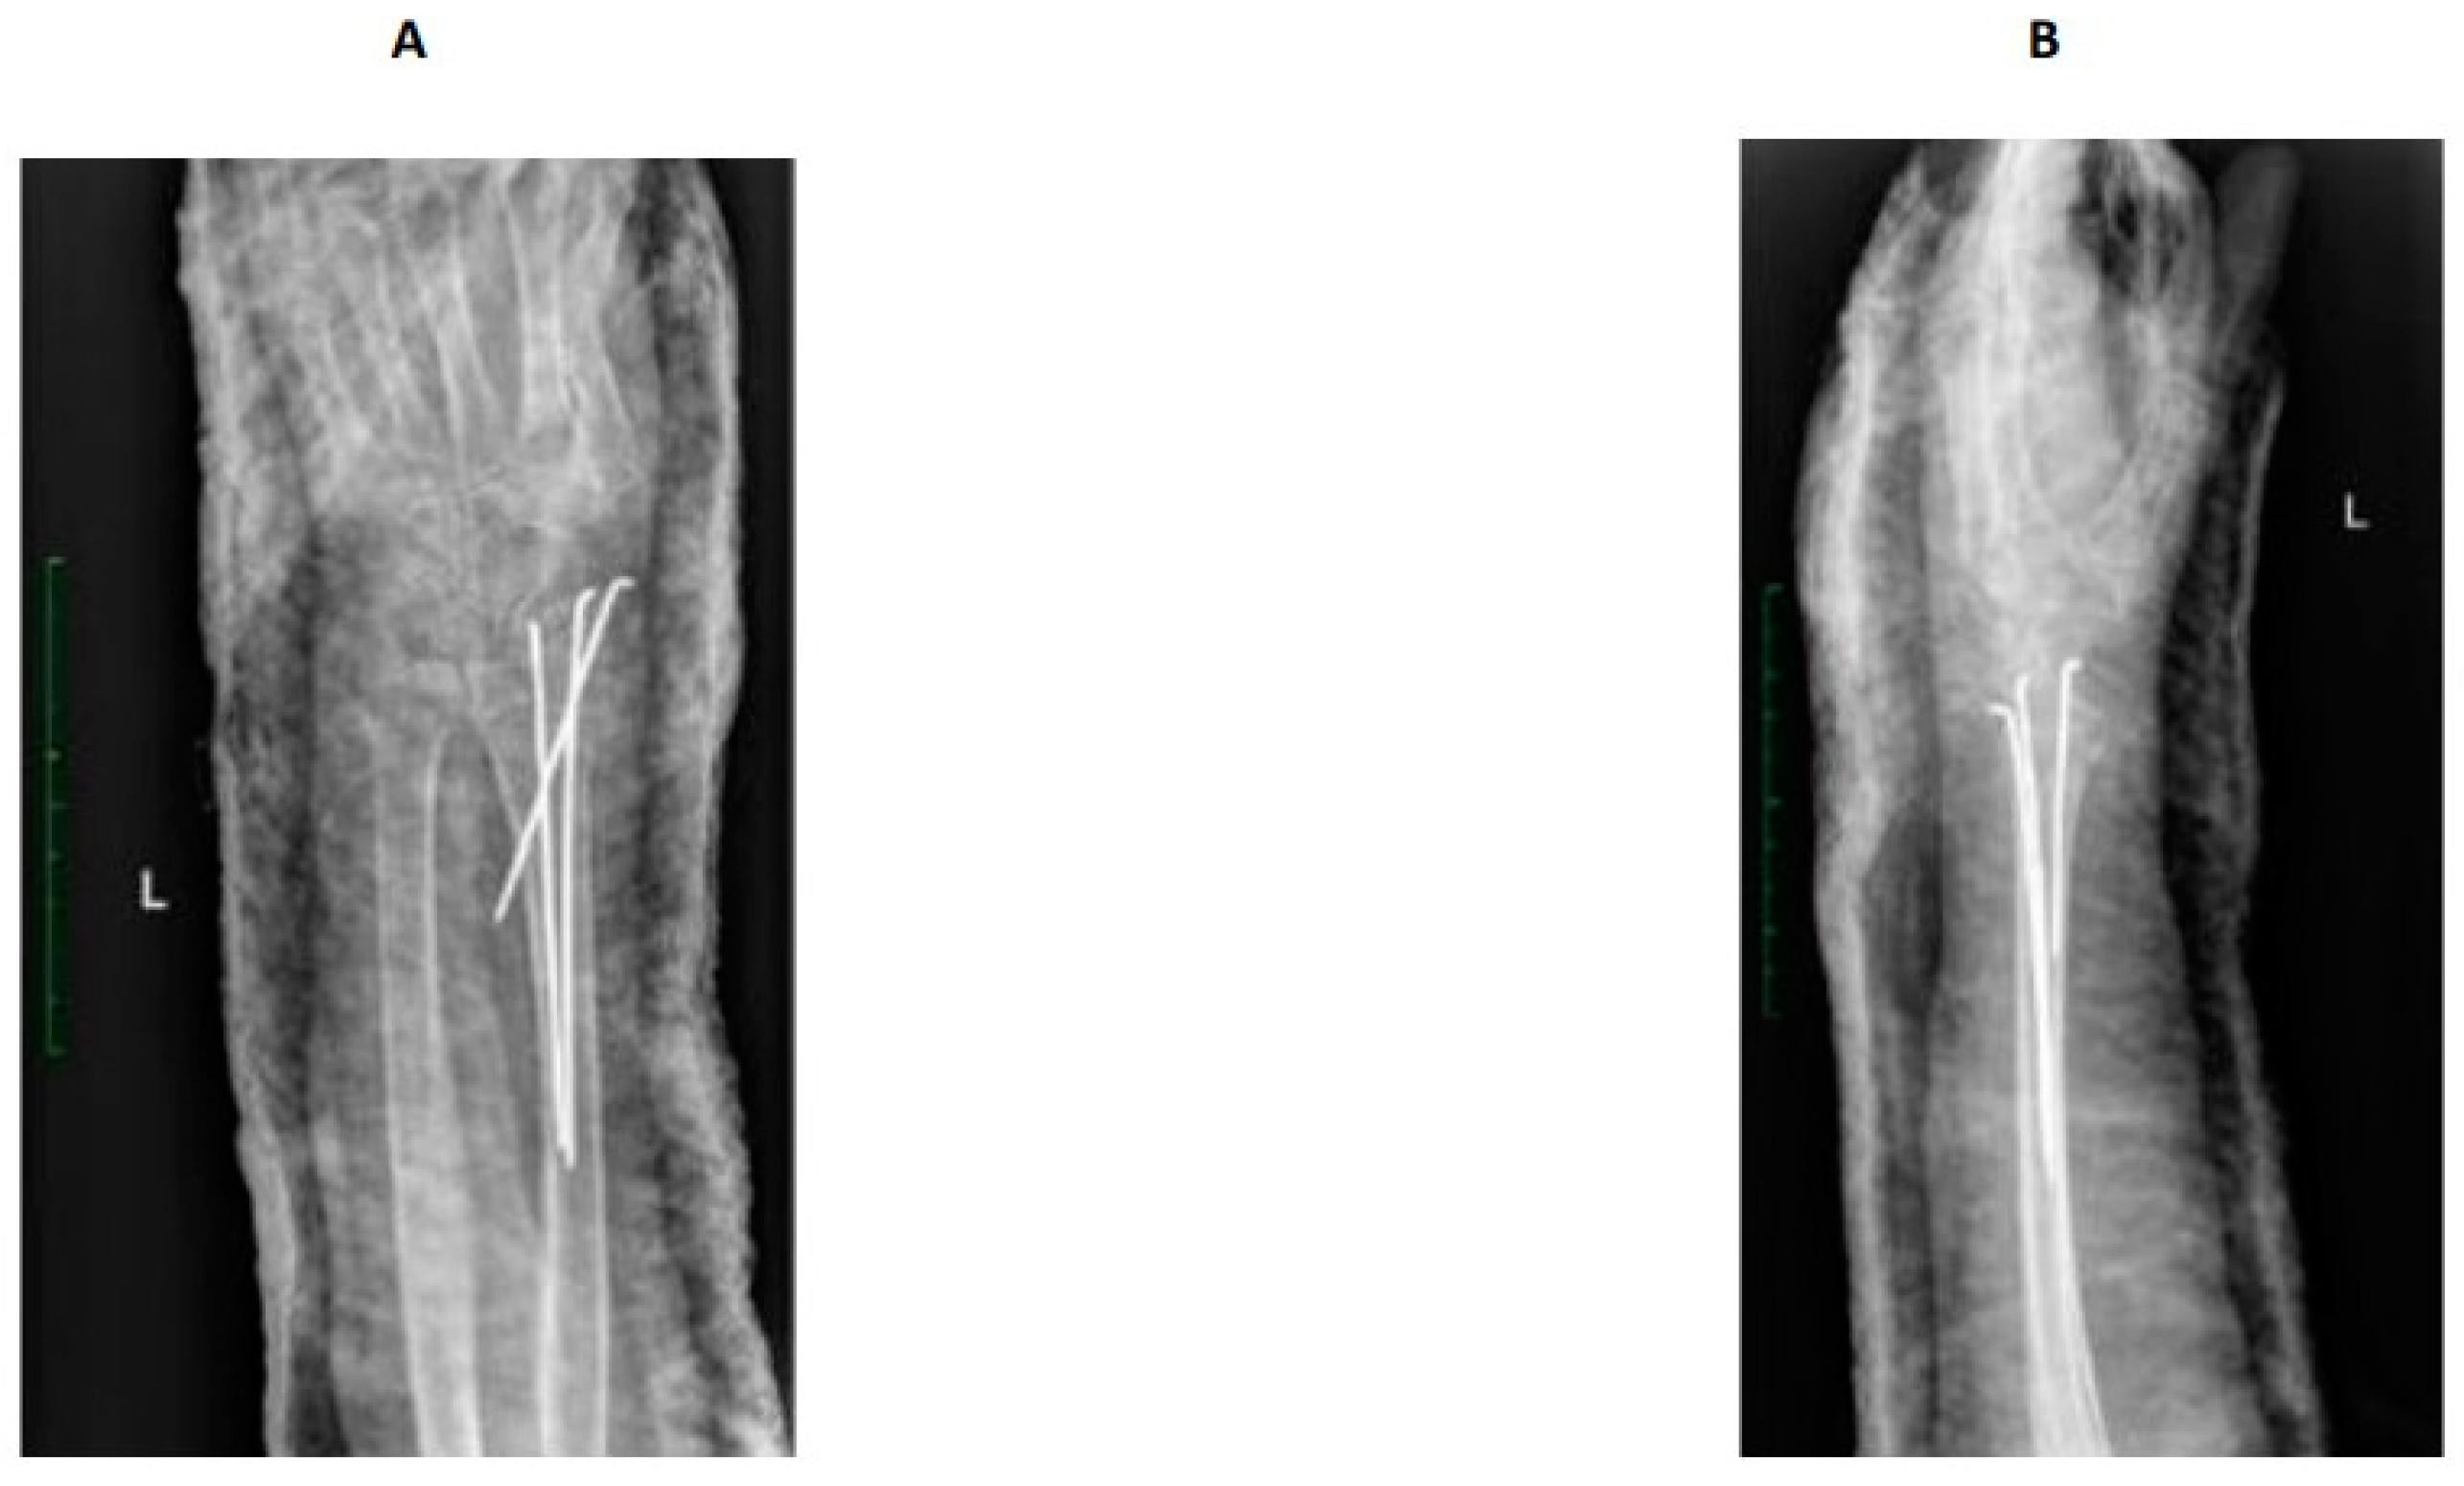

健康・医学 Distal Radius Fractures and Carpal Distal Radius Fractures and Acute Carpal Tunnel Syndromeの詳細情報

Distal Radius Fractures and Acute Carpal Tunnel Syndrome。Complex Regional Pain Syndrome after Distal Radius Fracture。Distal Radius fractures and acute Carpal tunnel syndrome。Acute Carpal Tunnel Syndrome in Pediatric Distal Radius。Distal Radius Fractures and Carpal Instabilities: FESSH IFSSH 2019 Instructional Book (English Edition)新品¥18,560Francisco del Pinal | 2019/6/24